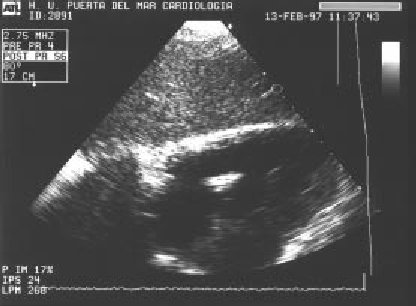

Figura 5.

- ETT de paciente con endocarditis infecciosa de la válvula tricúspide.